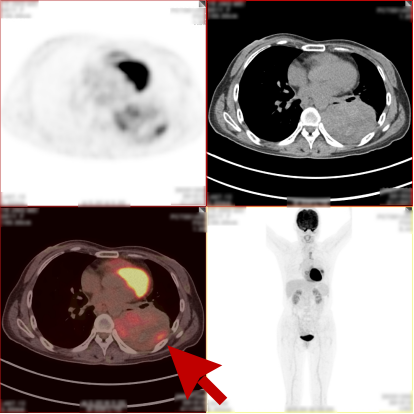

病史:女,51岁,左侧胸腔肿物约3-4年,干咳伴左侧胸痛1个月余,自服药物不能缓解。2023.12.6 CT 显示左侧胸腔及纵隔内肿块,考虑肿瘤性病变,胸膜来源低度恶性肿瘤(胸膜间皮瘤)可能。无其他病史,进食可,二便可,今年以来有体重减轻,为鉴别病灶良恶性申请PET/CT检查。

PET/CT检查所见

PET/CT诊断意见:

1、左侧胸腔内混杂密度肿块,实性组织代谢轻中度增高,考虑间叶组织来源低度恶性肿瘤,病灶内部分组织坏死,与左侧胸膜粘连并向纵隔内生长;

2、纵隔(1L、2L、3A、6、8R 组)及左侧锁骨上窝多发淋巴结转移灶;

3、胸 8 椎体左份结节状高代谢病灶,考虑骨转移灶。

PET/CT活检病理:恶性畸胎瘤